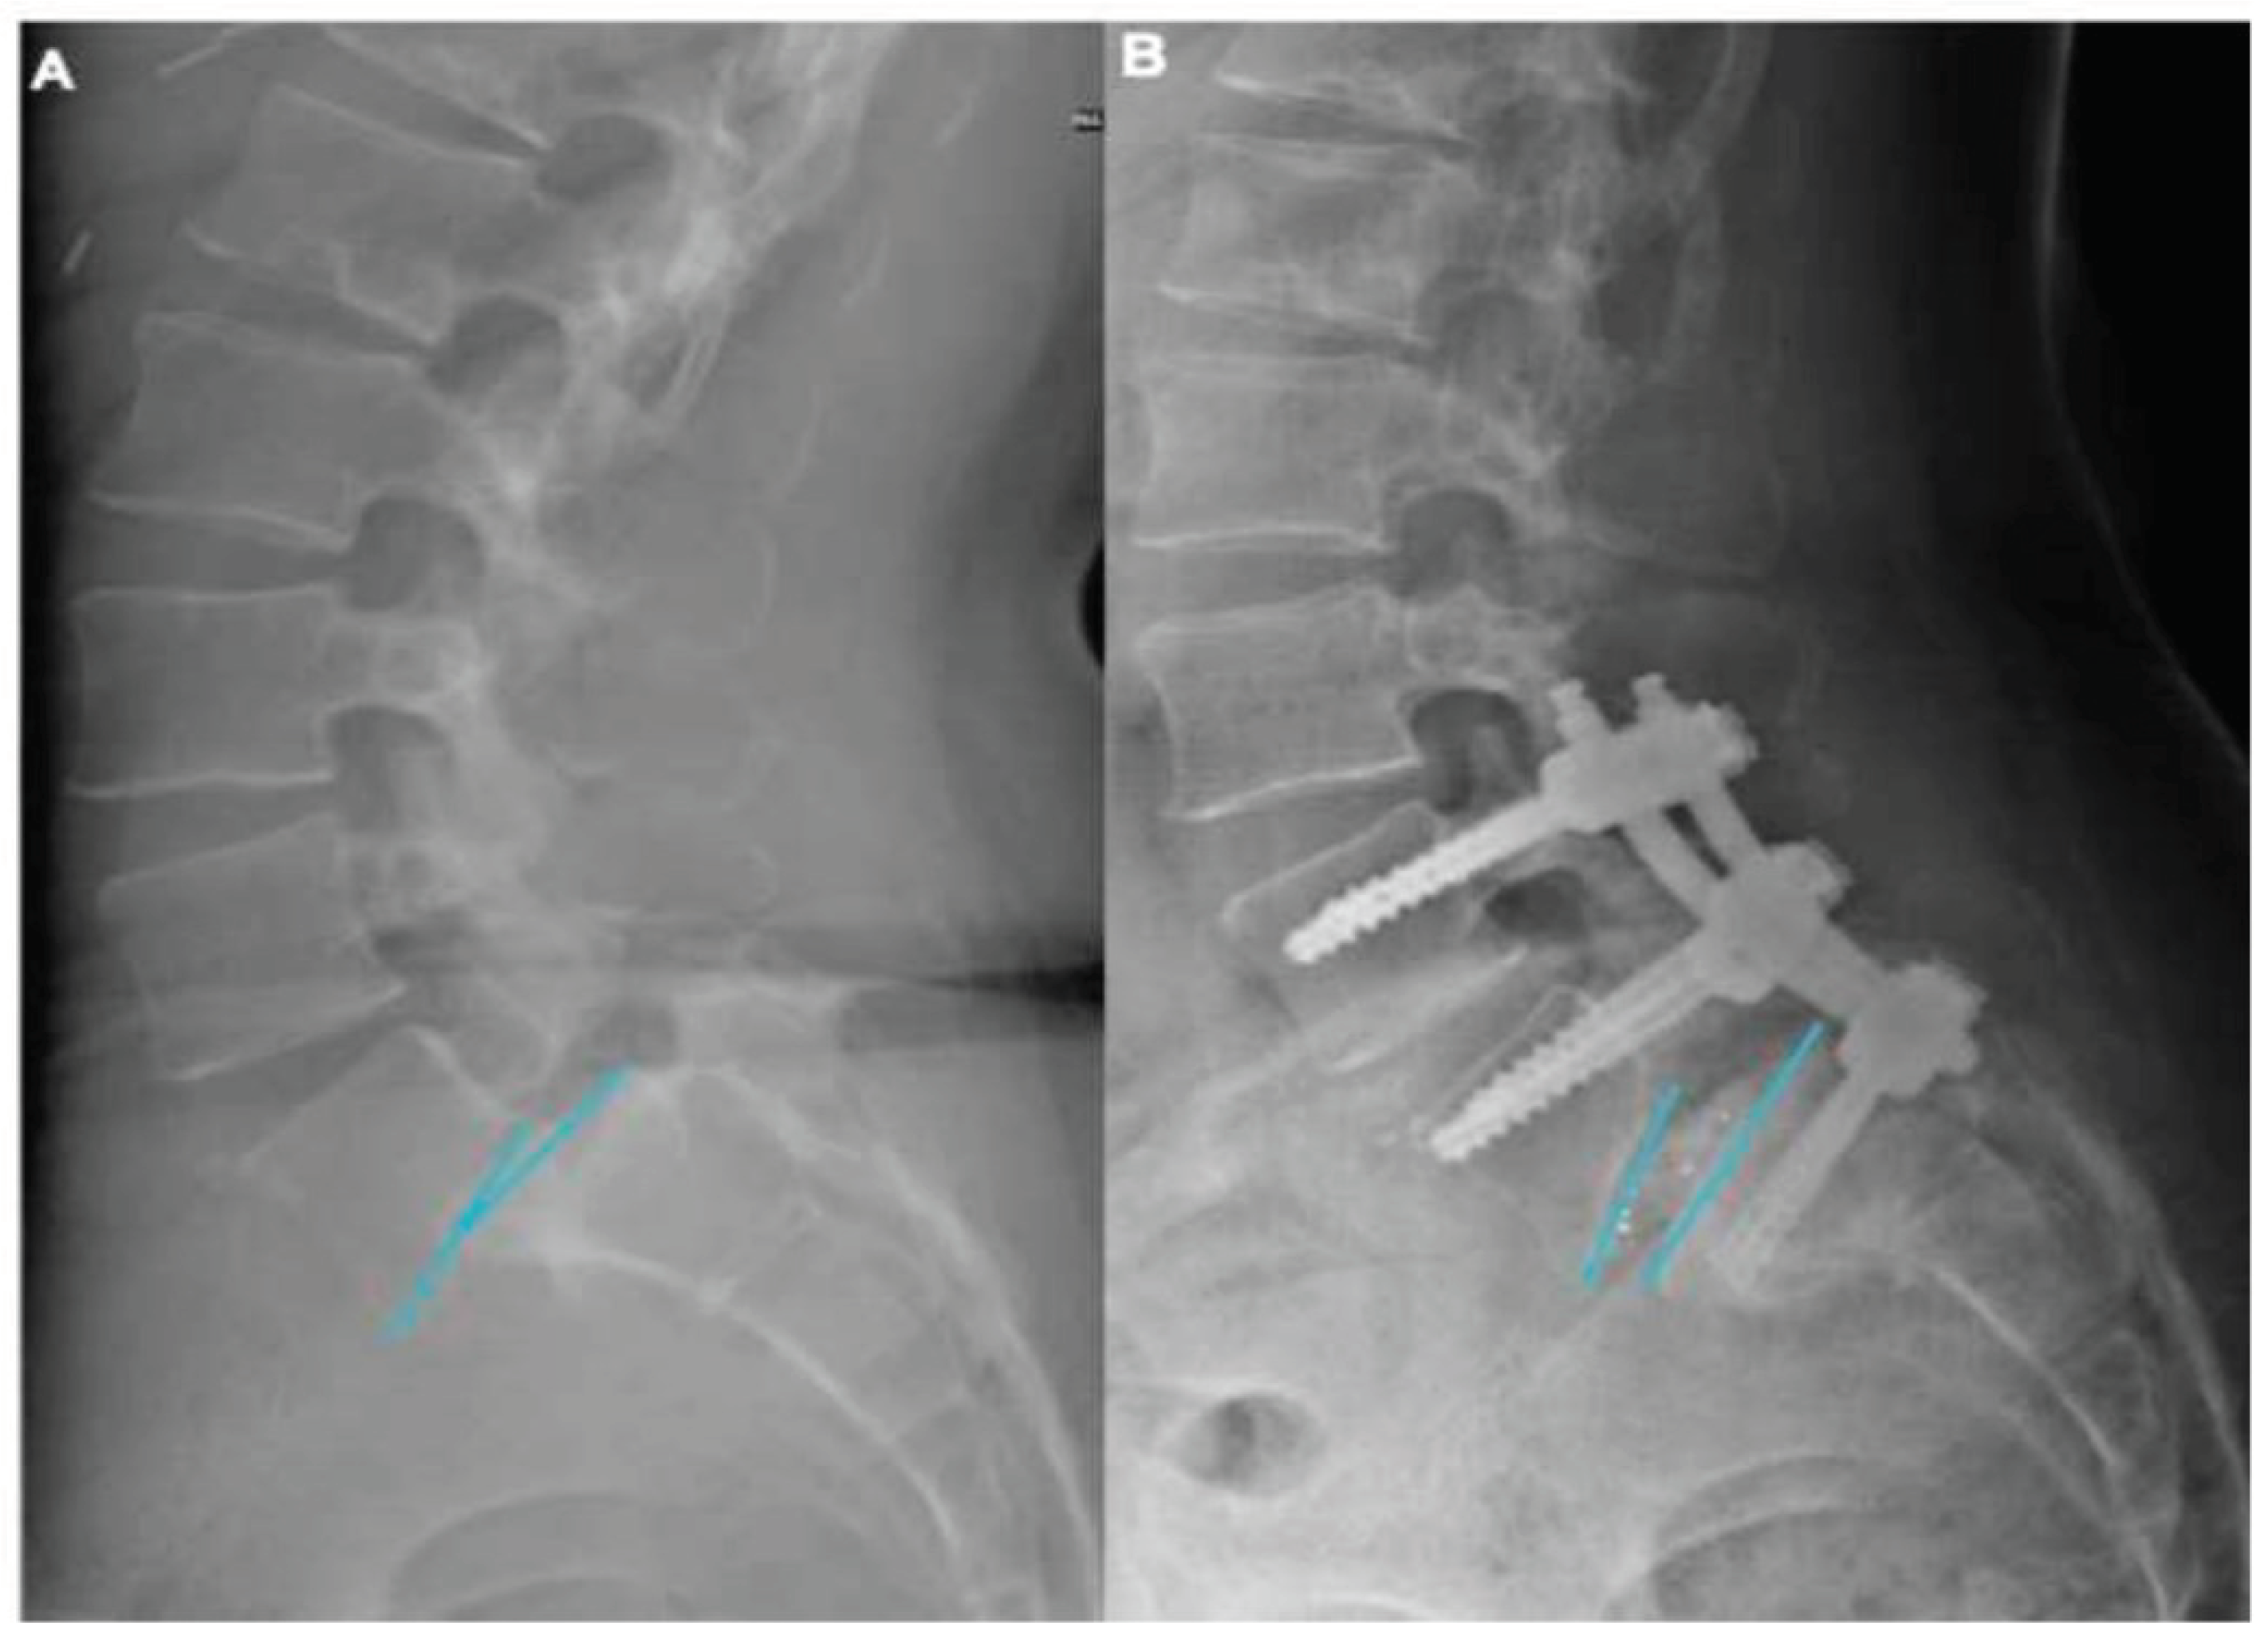

The mean changes at last follow-up evaluation were slippage 65 (±5)% (p = 0,02), slip angle 12 (±7) degrees (p=0,01), pelvic tilt 7 (±8) degrees (p<0,01). The sagittal vertical axis (SVA) was found in the range of normality [18] preoperatively and two years after surgery in all patients. No significative differences were found comparing pre- and post-operative thoracic kyphosis, lumbar lordosis, and pelvic incidence values. An illustrative case is showed in Figure 1. The univariate analysis showed that a slip angle > 10° (Figure 2) was the only independent factor, in our cohort of patients, in determining higher VAS-b and ODI scores (p=0,001 and p=0,03 respectively).

Slippage reduction may be often achieved using pedicle screws only, however, their capability in maintaining segmental correction has been already reported as lower than circumferential instrumentations, due to the higher risk of hardware failure [22]. Hence, the use of inter somatic cages, properly sized and positioned, may represent a key point in HGISL surgery, providing higher chances for a circumferential secondary fusion. Spinopelvic parameters restoration was associated with clinical improvement in patients with low-grade SL [4,14,23]. Our results suggest that a slip angle >10° is an independent factor in determining higher VAS-b and ODI scores. Accordingly, segmental deformity correction, even partial, may provide better long-term clinical outcomes; thus, it should be always pursued in HGISL patients with spinal malalignment.

Figure 2. Pre- and post-operative x-Ray lateral view for segmental slip angle evaluation. The preoperative (A) and postoperative (B) x-Rays lateral view of the same patient presented in Figure 1. The segmental slip angle (blue lines) changed from 13° (A) to 8° (B).